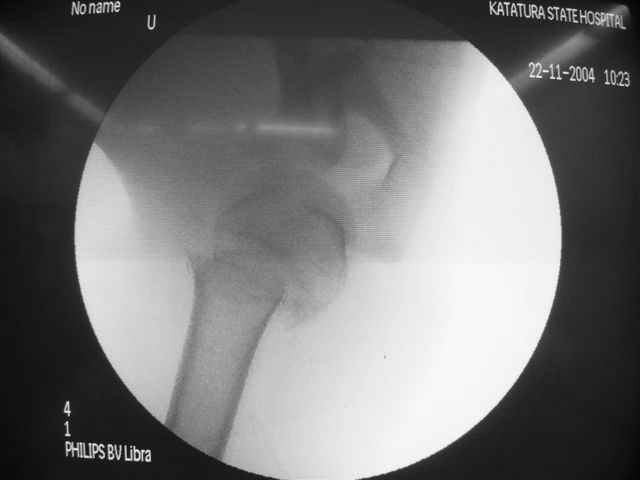

Пока я пользуюсь методикой принятой у нас (методика Сиэтла), также перкутанный спицевой метод, только сцицы 2.8 мм с резбой на конце.

Здесь случай перелома-вывиха плеча, больному 56 лет, после "дважды" закрытой неудачной репозиции, опять же ургентно взяли в операционную, после полного общего обезболивания попытались сделать репозицию, и фиксацию провели спицами.

Больной находился в повязке, примерно напоминяющей косыночную, рекомендованы движения в локтевом суставе и маятниковые движения в плече, спицы удалены в три недели (были случаи миграции)

Больной амбулаторный, предупрежден на случай осложнения АВН головки.